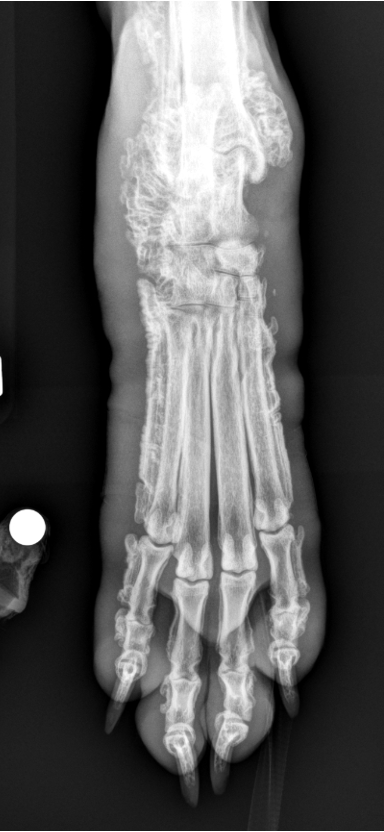

pedal osteitis

solar margin demineralizes

widening of vasc channels

septic osteitis

associated with solar abscesses and penetrating wounds

margin defect ± sequestrum

demineralized solar margin